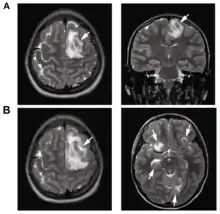

B: T1-weighted MRI showing expansion and addition of necrotic areas 4 days later

Granulomatous amoebic encephalitis (GAE)[2] is a rare, usually fatal, subacute-to-chronic central nervous system disease caused by certain species of free-living amoebae[3] of the genera Acanthamoeba, Balamuthia and Sappinia.[4][5] The term is most commonly used with Acanthamoeba. In more modern references, the term "balamuthia amoebic encephalitis" (BAE) is commonly used when Balamuthia mandrillaris is the cause.[6][7][8][9]